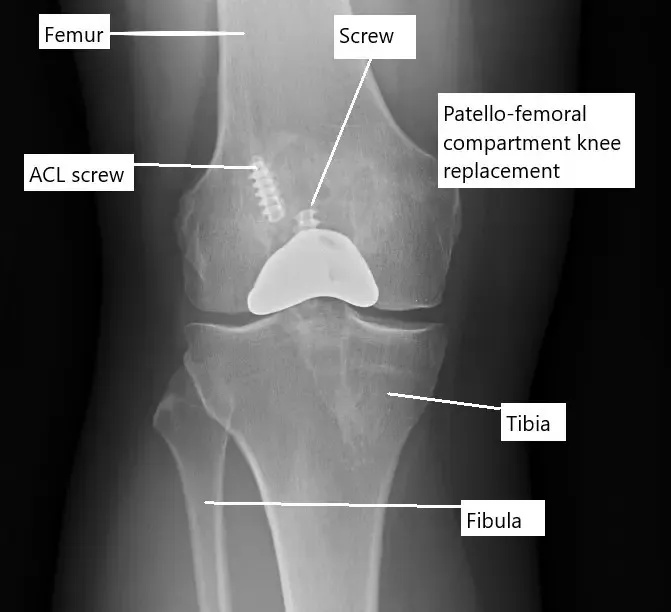

X-ray showing a partial knee replacement.

Partial knee replacement

In a partial knee replacement, only one of the compartments of the knee is replaced. During a partial knee replacement surgery, the surgeon accesses the joint through a usually smaller incision. The diseased ends of the bones forming the compartment are then cut to be removed. All the ligaments and other soft tissue structures are left intact.

A metal prosthetic component is placed on the cut bony ends and fixed with bone cement. A high-grade plastic part is placed in between the metal parts for the smooth gliding of the metal surfaces. The incision is closed in layers and the patient is able to walk the same day of the surgery.